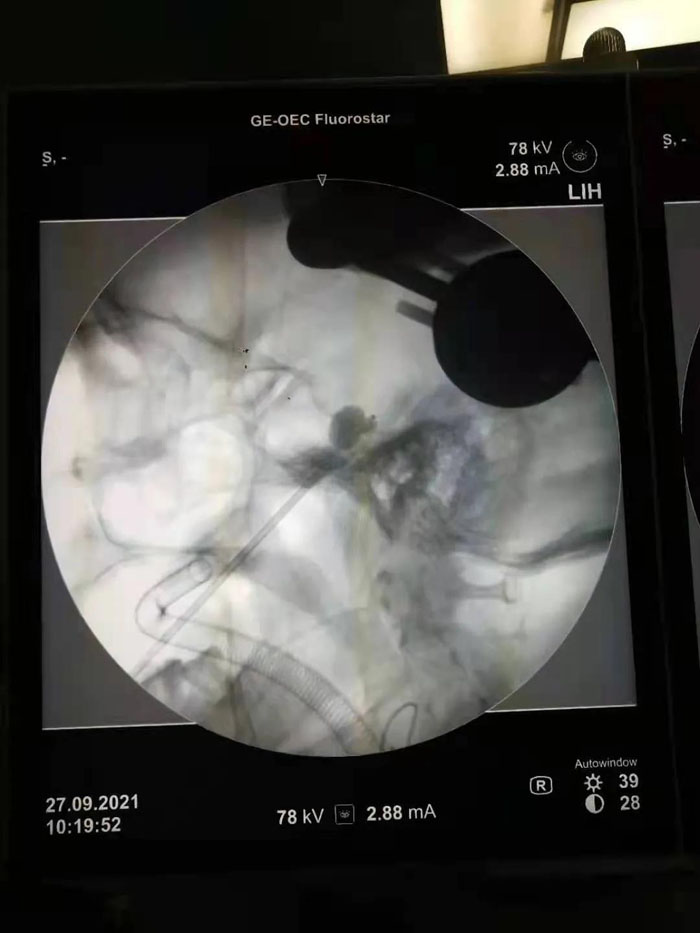

病例1.患者年近八旬,患有三叉神經(jīng)痛多年,疼痛發(fā)作起來痛不欲生,吃飯、洗臉都成了奢望。曾兩次到濟南某省級醫(yī)院行射頻、藥物注射等治療,無明顯效果。續(xù)繼軍主任團隊術(shù)前仔細研判患者病情,認為患者年齡大,開顱手術(shù)風險較高。三叉神經(jīng)半月節(jié)球囊壓迫術(shù)具有微創(chuàng)、恢復快、費用低的優(yōu)勢,更適合老年患者及復發(fā)患者。但該手術(shù)需要精確定位,手術(shù)最大的挑戰(zhàn)是要把穿刺針準確穿入近10cm外的卵圓孔,而該孔僅有3mm的大小,難度不亞于射擊比賽中“百步穿楊”。傳統(tǒng)方法只能在C形臂引導下徒手進行,穿刺成功率低。在續(xù)繼軍主任指導下,丁鵬、吳開福主治醫(yī)師采用機器人輔助穿刺,術(shù)前驗證誤差僅為0.37mm,保證了一針穿刺到位,實際術(shù)中僅用10秒鐘即完成了穿刺操作,避免了重要血管、腦組織的損傷,大大降低了手術(shù)風險。術(shù)后,患者面部疼痛即基本消失,2天后順利出院。